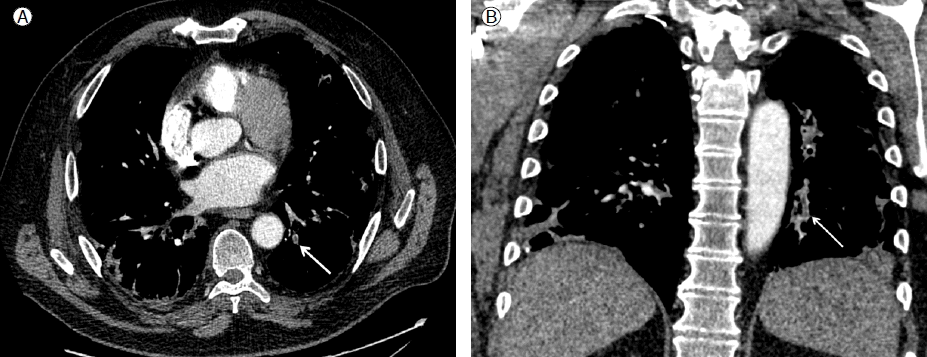

이 결과를 확인 후 폐경색의 원인 규명을 위해 본원에서 흉부 컴퓨터 단층촬영(pulmonary thromboembolism protocol CT)을 시행하였고 세분절(subsegmental) 폐동맥 부위의 혈전이 확인되었다(Fig. 4).